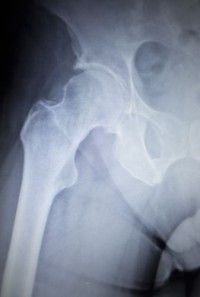

metal-hip-implantA metal hip complications lawsuit was filed against Zimmer Inc. for allegedly causing a California woman to suffer debilitating injuries.

Janet F., who brought the lawsuit with her husband, was suffering from hip pain and decided to get a hip replacement.

After reading the defendant’s advertisements for its Durom Cup, the lawsuit says, Janet underwent hip implant surgery on March 28, 2008. Not long after the hip surgery, the plaintiff started complaining of pain, which became so bad that it interfered with her daily activities, the metal hip lawsuit says.